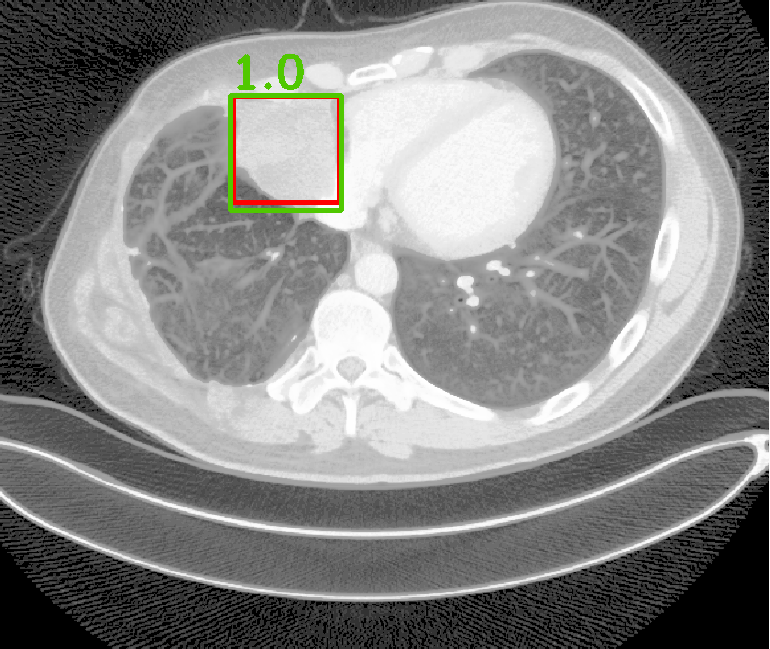

| (a) Ground Truth | (b) Faster R-CNN | (c) FPN | (d) Proposed |

In real-world scenarios, body lesions usually have arbitrary size. For instance, in the DeepLesion [14] dataset, the lesion size ranges from 0.21 mm to 342.5 mm. Since most of the established CNNs are not robust to handle such spatial scale variations, they have unpredictable behavior in the varying cases. As shown in Fig. 1, both Faster R-CNN and FPN fail to detect tiny lesions in the first row, while they produce small false positive lesions around the actual large lesion locations in the second and third rows.

In this paper, we propose a fine-grained lesion detection approach with a novel multi-scale attention mechanism. We use 2D FPN as the backbone to construct the feature pyramid in a relatively coarse scale. Within each level of the feature pyramid, we propose to use a Multi-Scale Booster (MSB) to facilitate lesion detection across fine-grained scales. Given the feature maps from one pyramid level, MSB first performs Hierarchically Dilated Convolution (HDC) that consists of several dilated convolution operations with different dilation rates [15]. The feature responses from HDC contain fine-grained information that is complementary to the original feature pyramid, which is achieved by extensive feature extraction in 2D space. The over-sampled feature responses are then concatenated and further exploited by channel-wise and spatial-wise attention. The channel attention module in MSB explores different lesion responses from the subchannels of the concatenated feature maps. The spatial attention module in MSB locates lesion response within each attentive channel. The channel-wise and spatial-wise attention modules enable the network to focus on particular lesion responses offered by the fine-grained features, while annealing the irrelevant and interference information. Thorough experiments demonstrate that MSB improves the deep pyramid prediction results and performs favorably against state-of-the-art approaches on the DeepLesion benchmarks.